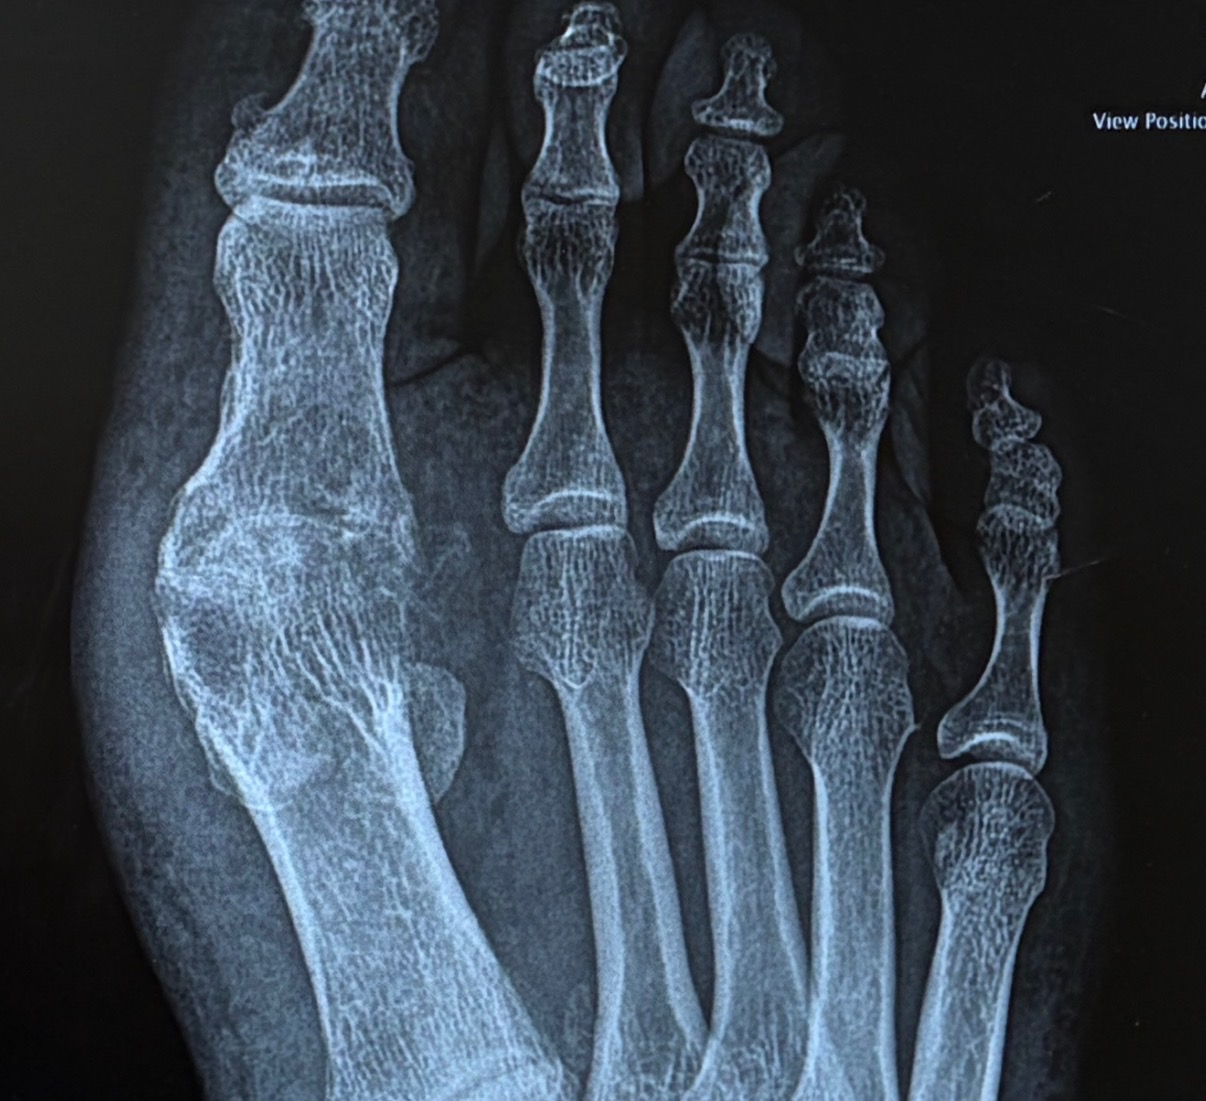

AP (Anteroposterior) View

Based on the radiographic images provided, this appears to be a case of hallux rigidus (degenerative arthritis of the first metatarsophalangeal joint).

1. Joint Space Narrowing - Significant narrowing of the first MTP (metatarsophalangeal) joint space - Indicates cartilage loss and degenerative changes - Most prominent at the dorsal (top) aspect of the joint

2. Osteophyte Formation - Visible bone spurs (osteophytes) at the joint margins - Particularly prominent on the dorsal aspect of the first metatarsal head - Classic sign of osteoarthritis in this location

3. Subchondral Sclerosis - Increased bone density (sclerosis) adjacent to the joint surface - Indicates chronic stress and remodeling - Visible as brighter/whiter bone on the x-ray

4. Joint Alignment - Overall alignment appears maintained - No significant hallux valgus (bunion) deformity - Sesamoid bones appear intact

Based on radiographic findings, this appears to be Grade 2-3 hallux rigidus: - Grade 1: Mild osteophytes, minimal joint space narrowing - Grade 2: Moderate osteophytes, joint space narrowing, subchondral sclerosis - Grade 3: Severe osteophytes, marked joint space narrowing, cyst formation - Grade 4: Complete joint destruction